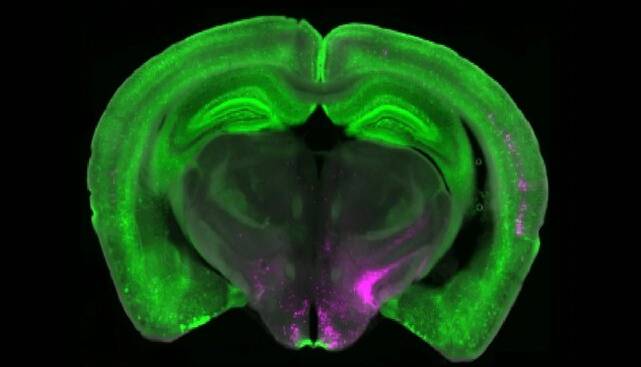

گروه بتلی با همکاری پژوهشگران «آزمایشگاه تیلور»(Taylor lab) در دانشگاه پیتسبرگ، از تصویربرداری کلسیم برای به تصویر کشیدن در لحظه فعالیت نورون‌ها در مدل‌های حیوانی درد کوتاه‌مدت و بلندمدت استفاده کردند. آنها دریافتند که نورون‌های Y1R صرفاً به حملات سریع درد واکنش نشان نمی‌دهند، بلکه در طول درد بلندمدت به طور پیوسته فعال می‌شوند. این پدیده‌ به عنوان «فعالیت تونیک»(Tonic activity) شناخته می‌شود.

این اطلاعات، الهام‌بخش تحقیقات بیشتر شدند. «نیتسان گلدشتاین»(Nitsan Goldstein)، دانشجوی سابق کارشناسی ارشد دانشگاه پنسیلوانیا دریافت که سایر حالت‌های حیاتی بقا مانند تشنگی و ترس نیز می‌توانند درد بلندمدت را سرکوب کنند. این گروه پژوهشی با همکاری «آزمایشگاه کندی»(Kennedy lab) در مؤسسه پژوهشی اسکریپس نشان دادند که وقتی بقای فوری در اولویت قرار می‌گیرد، هسته پارابراکیال مغز می‌تواند ورودی‌های حسی را نسبت به درد آرام فیلتر کند.

پژوهشگران در این پروژه، هویت مولکولی و آناتومیکی نورون‌های Y1R را در هسته پارابراکیال مشخص کردند. آنها دریافتند که نورون‌های Y1R، دو جمعیت آناتومیکی یا مولکولی منظم را تشکیل نمی‌دهند. در عوض، این نورون‌ها در بسیاری از انواع سلول‌های دیگر پراکنده شده‌اند.

بتلی گفت: این مانند نگاه کردن به خودروها در یک پارکینگ است. ما انتظار داشتیم همه نورون‌های Y1R به صورت خوشه‌ای از خودروهای زرد باشند که در کنار یکدیگر پارک شده‌اند، اما در اینجا نورون‌های Y1R مانند رنگ زردی هستند که در میان خودروهای قرمز، آبی و سبز پراکنده شده‌اند. ما دقیقاً نمی‌دانیم چرا، اما فکر می‌کنیم این توزیع پراکنده ممکن است به مغز امکان دهد تا انواع گوناگون ورودی‌های دردناک را در مدارهای متعدد تعدیل کند.